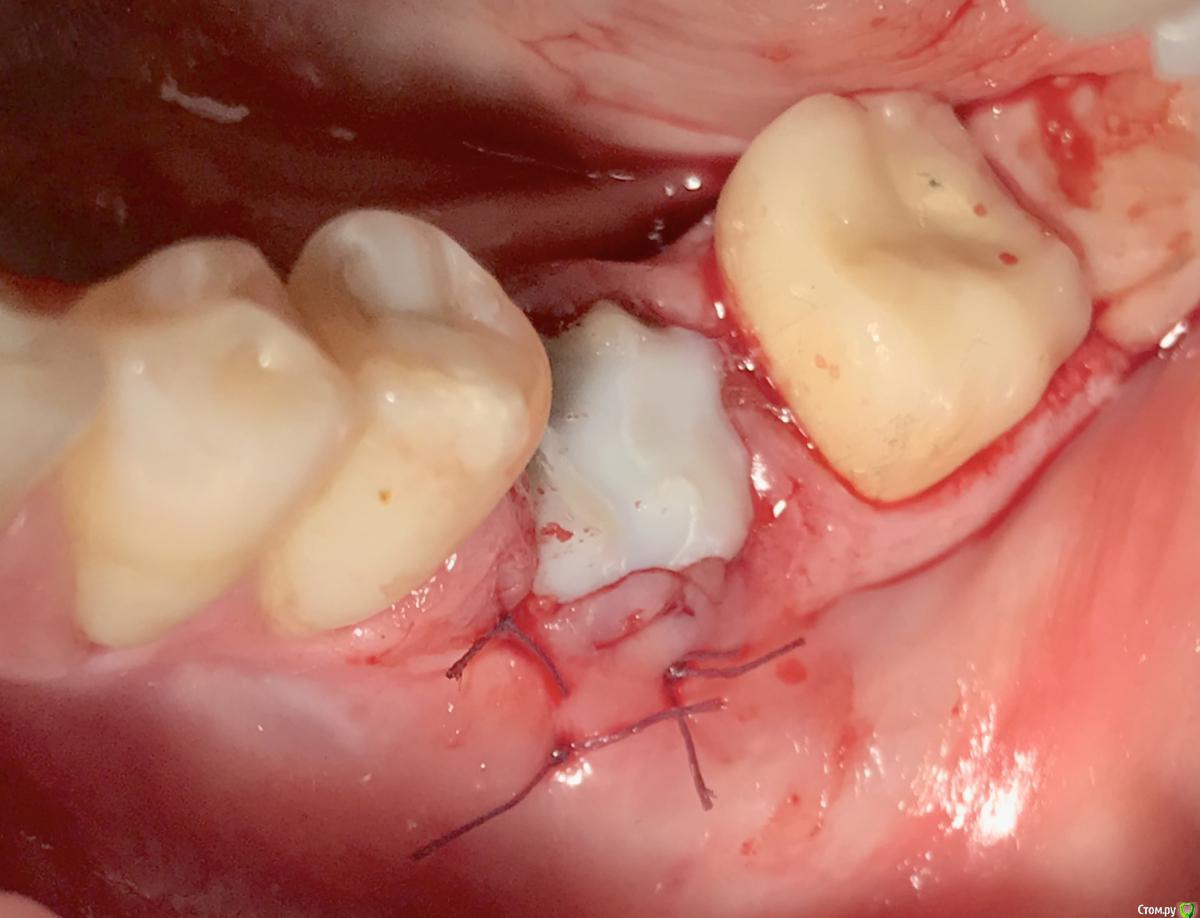

колесников Опубликовано 22 апреля, 2019 Поделиться Опубликовано 22 апреля, 2019 (изменено) И снова профайл спасает жизнь (облегчает жизнь имплантолога)Стандартная ситуация:36 периодонтит в стадии обострения с грануляциями,эксудацией,резорбцией компактной пластинки,дефицитом прикреплённой слизистой вестибулярного. Одна хирургия. Ноябрь 2018. Удаление,кюретаж,имплант Astra tech profile 4.5x9 под заглушку,торк около нуля. Вестибулярного сст,консервация графтом Sureoss 0,5 чипс с APRF,закрытие шайбой по Ноймайеру. Через неделю шайба несостоятельна-удалена. Пациентка созрела на удаление 37го. Выполнена декоронация в связи с отъездом пациентки,далее через 2 недели удаление и имплантация 37го. Промежуточный осмотр в январе. В марте установлены формирователи . Апрель контрольный осмотр. Периотест -5. Направлена на протезирование. Изменено 22 апреля, 2019 пользователем колесников 4 Ссылка на комментарий

колесников Опубликовано 23 апреля, 2019 Автор Поделиться Опубликовано 23 апреля, 2019 в стадии обострения, эт канэш яйца у тебя из титана ))) 1) "шайба" сверху залита композитом?2) как либо фиксировалась "шайба"?3) декоронация для чего? (чтобы больше слизистой наросла) Про обострение-это стандартный протокол1) залита композитом 2)фиксировалась швами3)чтобы больше слизистой наросло Ссылка на комментарий